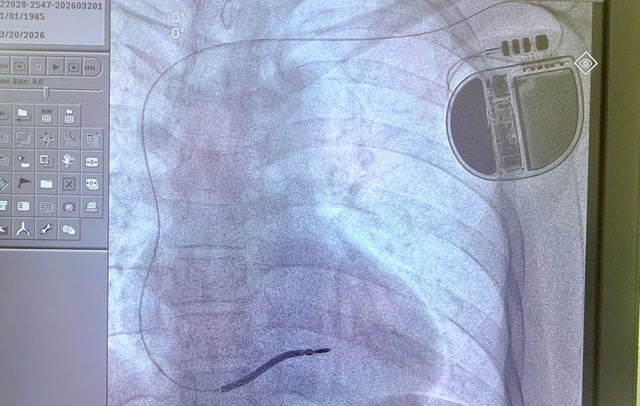

Các bác sĩ Khoa Tim mạch can thiệp, Bệnh viện Đa khoa khu vực Thủ Đức vừa lần đầu tiên thực hiện thành công kỹ thuật cấy máy phá rung tim tự động (ICD), cứu sống một bệnh nhân 41 tuổi mắc hội chứng Brugada type 1 – bệnh lý có nguy cơ đột tử cao.

Sau hội chẩn, các bác sĩ quyết định thực hiện cấy máy phá rung tim tự động (ICD) – phương pháp hiệu quả nhất hiện nay để phòng ngừa đột tử ở bệnh nhân nguy cơ cao.

Đây là kỹ thuật chuyên sâu trong tim mạch can thiệp, đòi hỏi trang thiết bị hiện đại và đội ngũ bác sĩ nhiều kinh nghiệm. Đặc biệt, đây cũng là lần đầu tiên kỹ thuật này được triển khai tại Bệnh viện Đa khoa khu vực Thủ Đức.

Thiết bị ICD có khả năng theo dõi nhịp tim liên tục, phát hiện sớm các cơn loạn nhịp nguy hiểm và tự động phát xung điện để đưa nhịp tim trở lại bình thường, qua đó ngăn ngừa đột tử.